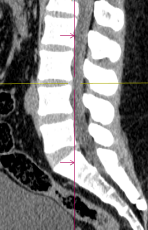

Nghiêng kỹ thuật số ±50° giúp quy trình nhanh hơn.

Chỉ với 1 click tự động xác định chính xác phạm vi quét theo giao thức đã chọn, giảm thiểu điều chỉnh thủ công phức tạp

Chỉ với 1 click định vị chính xác iso-center, tối ưu hình ảnh và liều tia, giảm thiểu phơi nhiễm